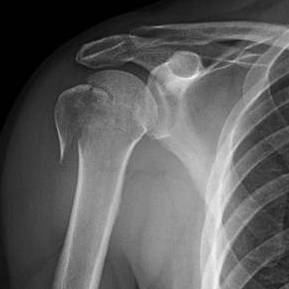

كسور نهاية الترقوة البعيدة هي إصابات شائعة تصيب الكتف، وغالبًا ما تحدث نتيجة السقوط أو الإصابة المباشرة. يعتمد أفضل عل…